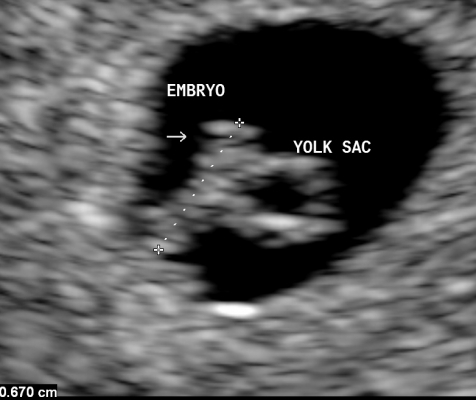

What An Early Pregnancy Ultrasound May Be Able To Detect

• Determine how far along you are and provide an estimated due date.

• Confirm that your pregnancy is progressing as expected and that the baby is in the right place.